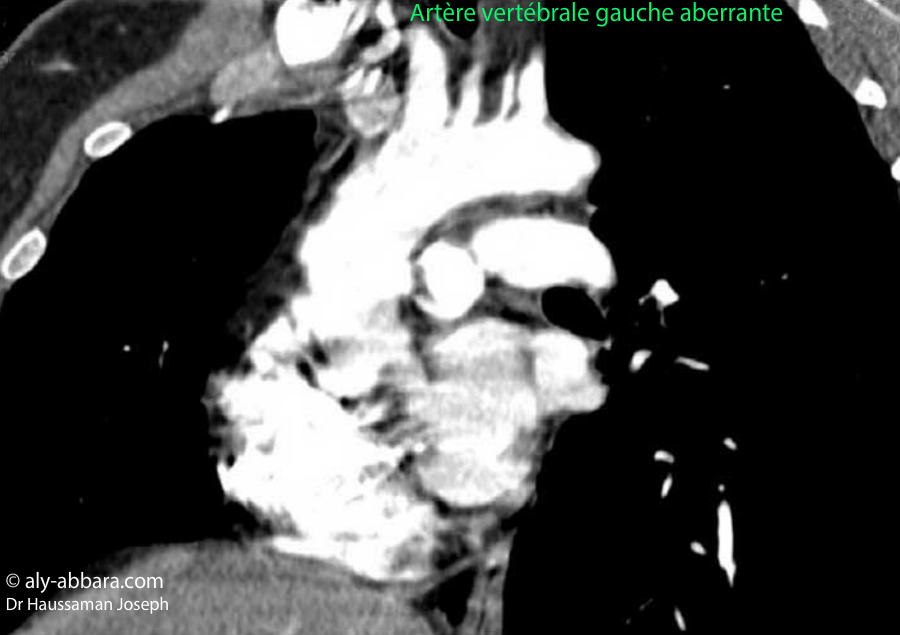

Images-scanner montrant un cas d'artère vertébrale gauche aberrante naissant

directement de l'arc aortique au lieu de naître de l'artère subclavière gauche.

• Dans le cas présent, de la crosse de l'aorte naissent successivement quatre vaisseaux artériels :

• 1- le tronc artériel brachio-céphalique qui se divise en deux artères :

• l'artère carotide commune droite ;

• l'artère subclavière (sous-claviculaire) droite.

• L'artère vertébrale droite est une branche de l'artère subclavière droite.

• 2- l'artère carotide commune gauche ;

• 3- l'artère vertébrale gauche ;

• 4- l'artère subclavière gauche.

• Donc chez cette personne, l'artère vertébrale gauche est aberrante parce qu'elle naît directement de l'arc aortique au lieu de naître de l'artère subclavière gauche.